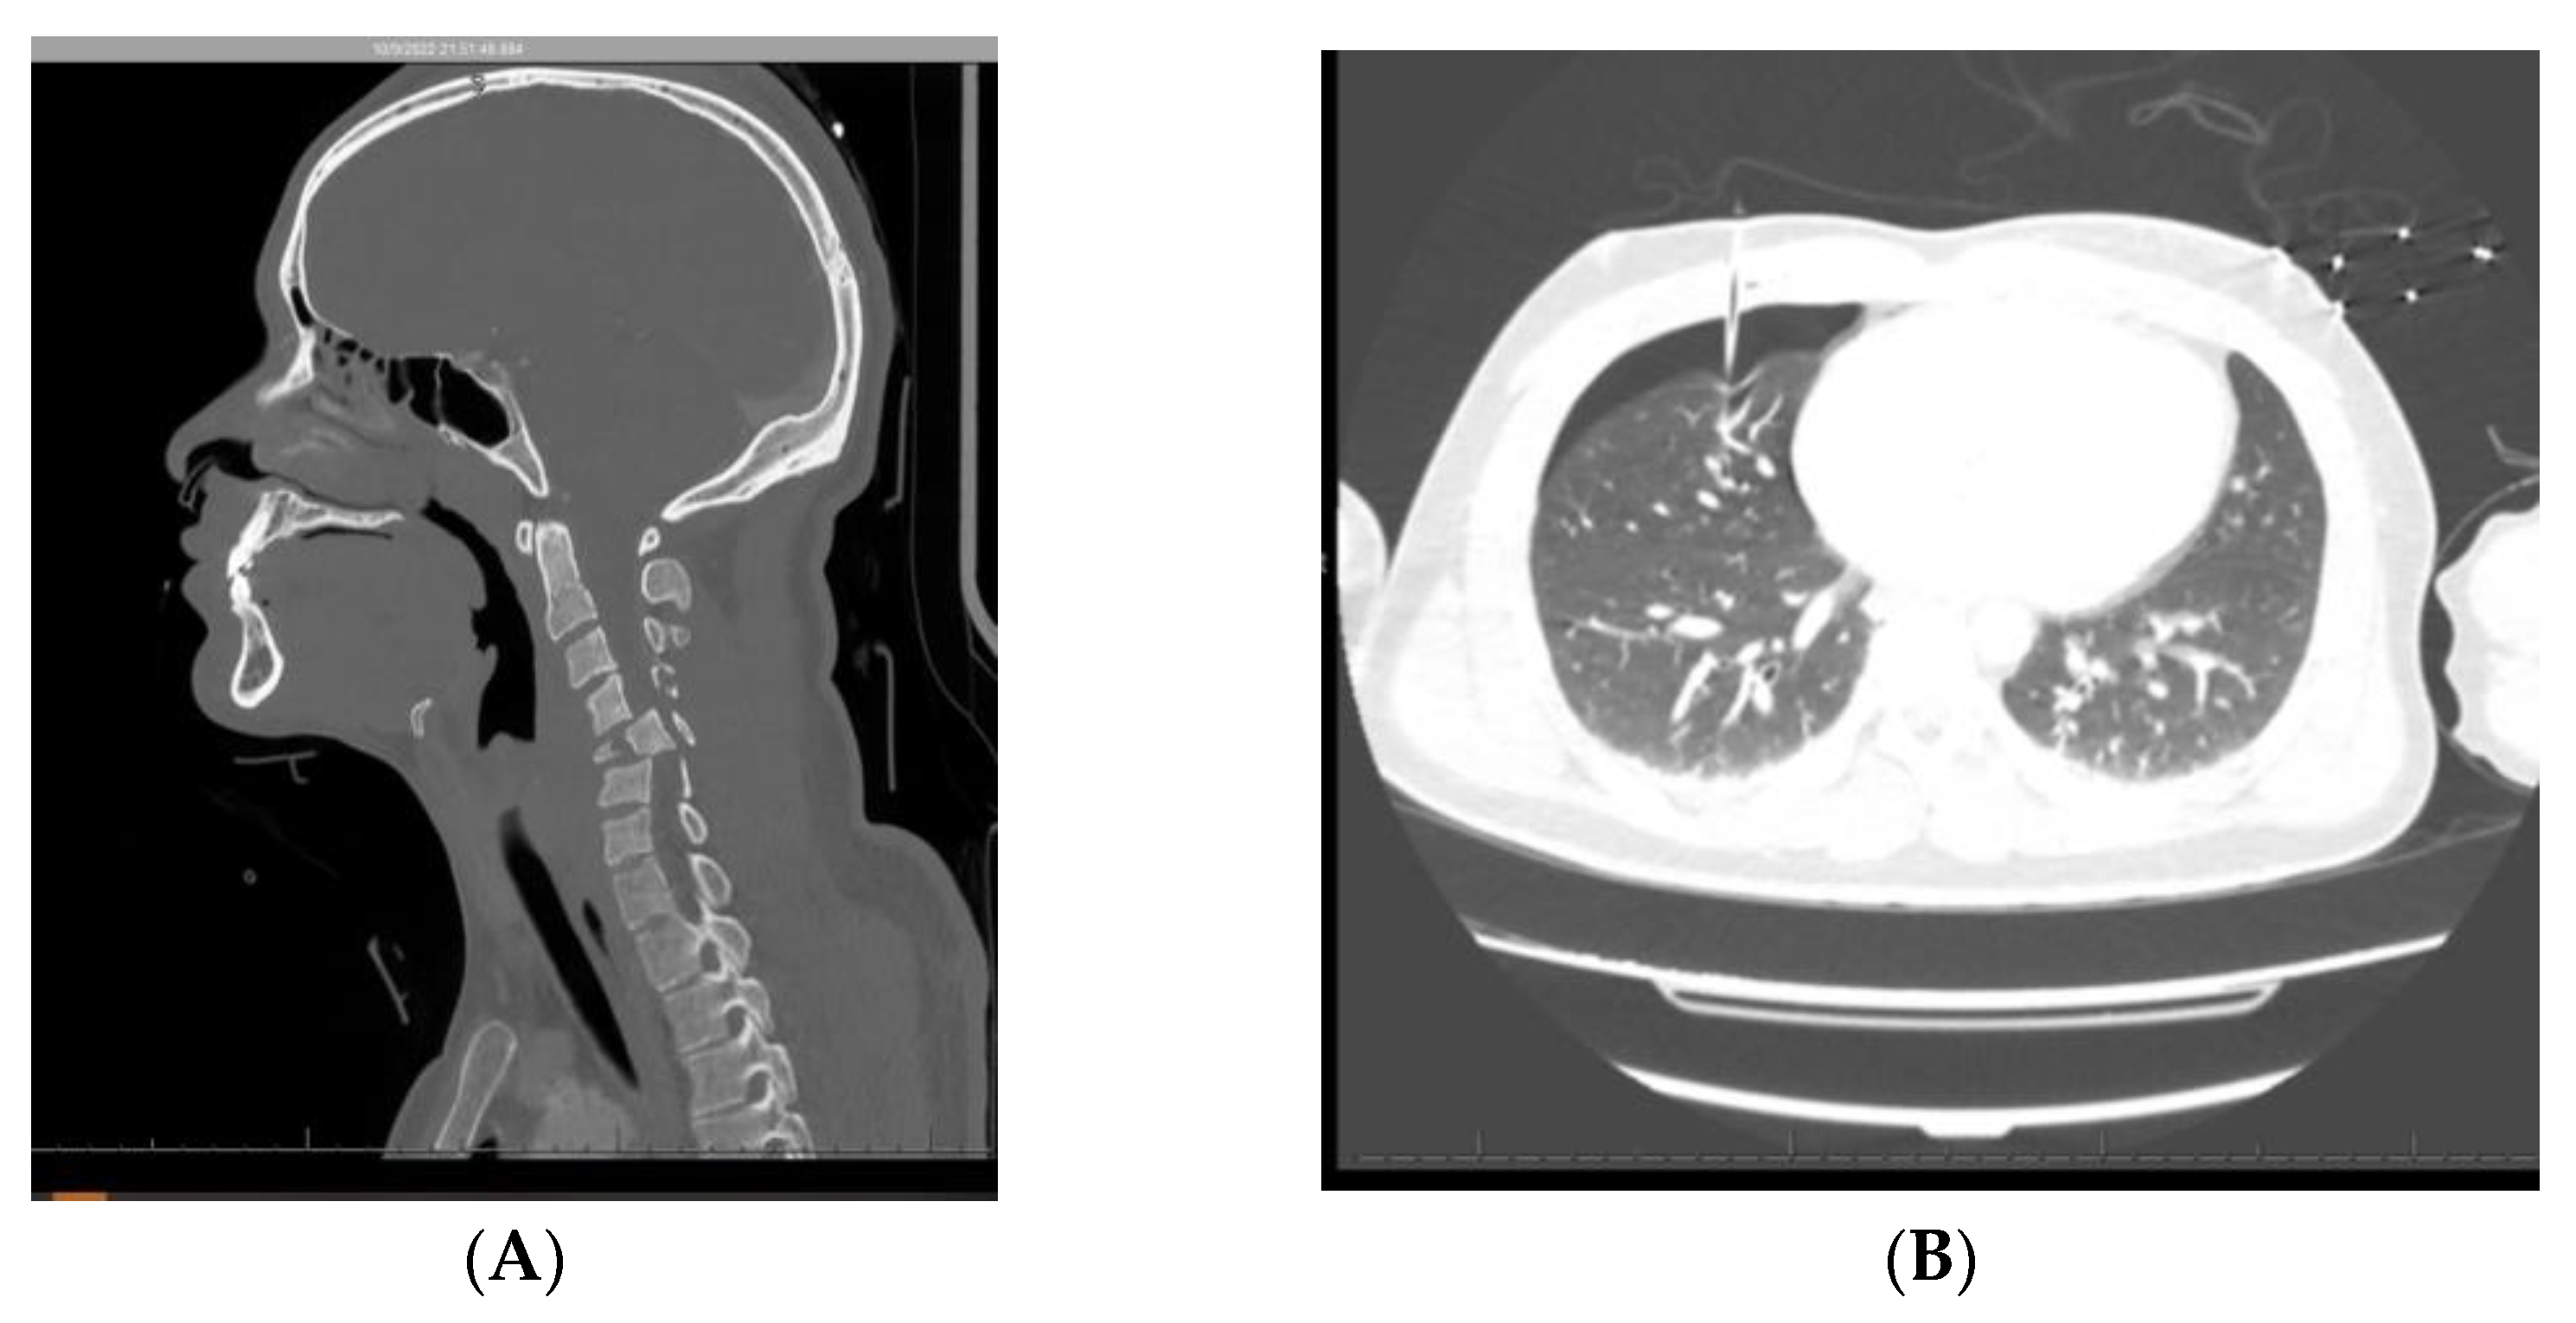

6.1. Case 1